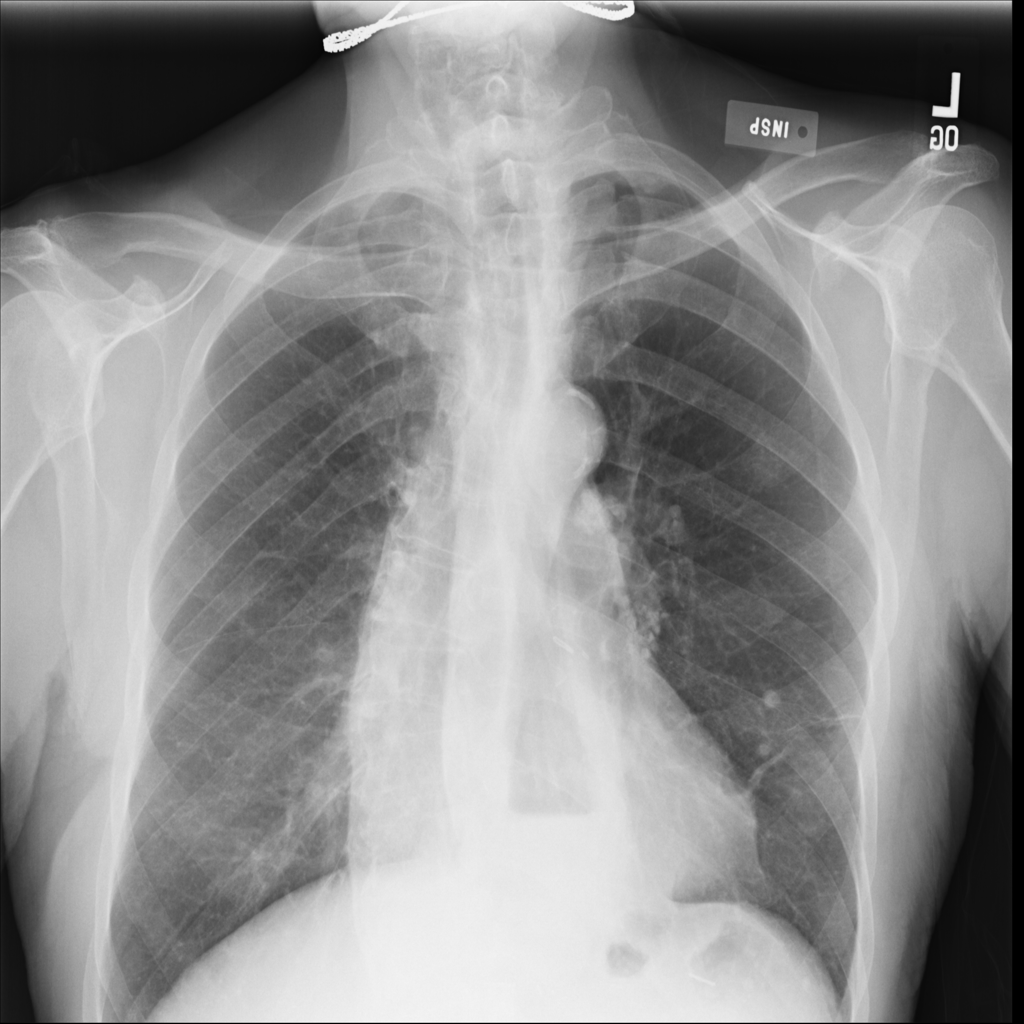

PAT-C048 · IMG-001Hernia

PAT-C048 · IMG-001

PA